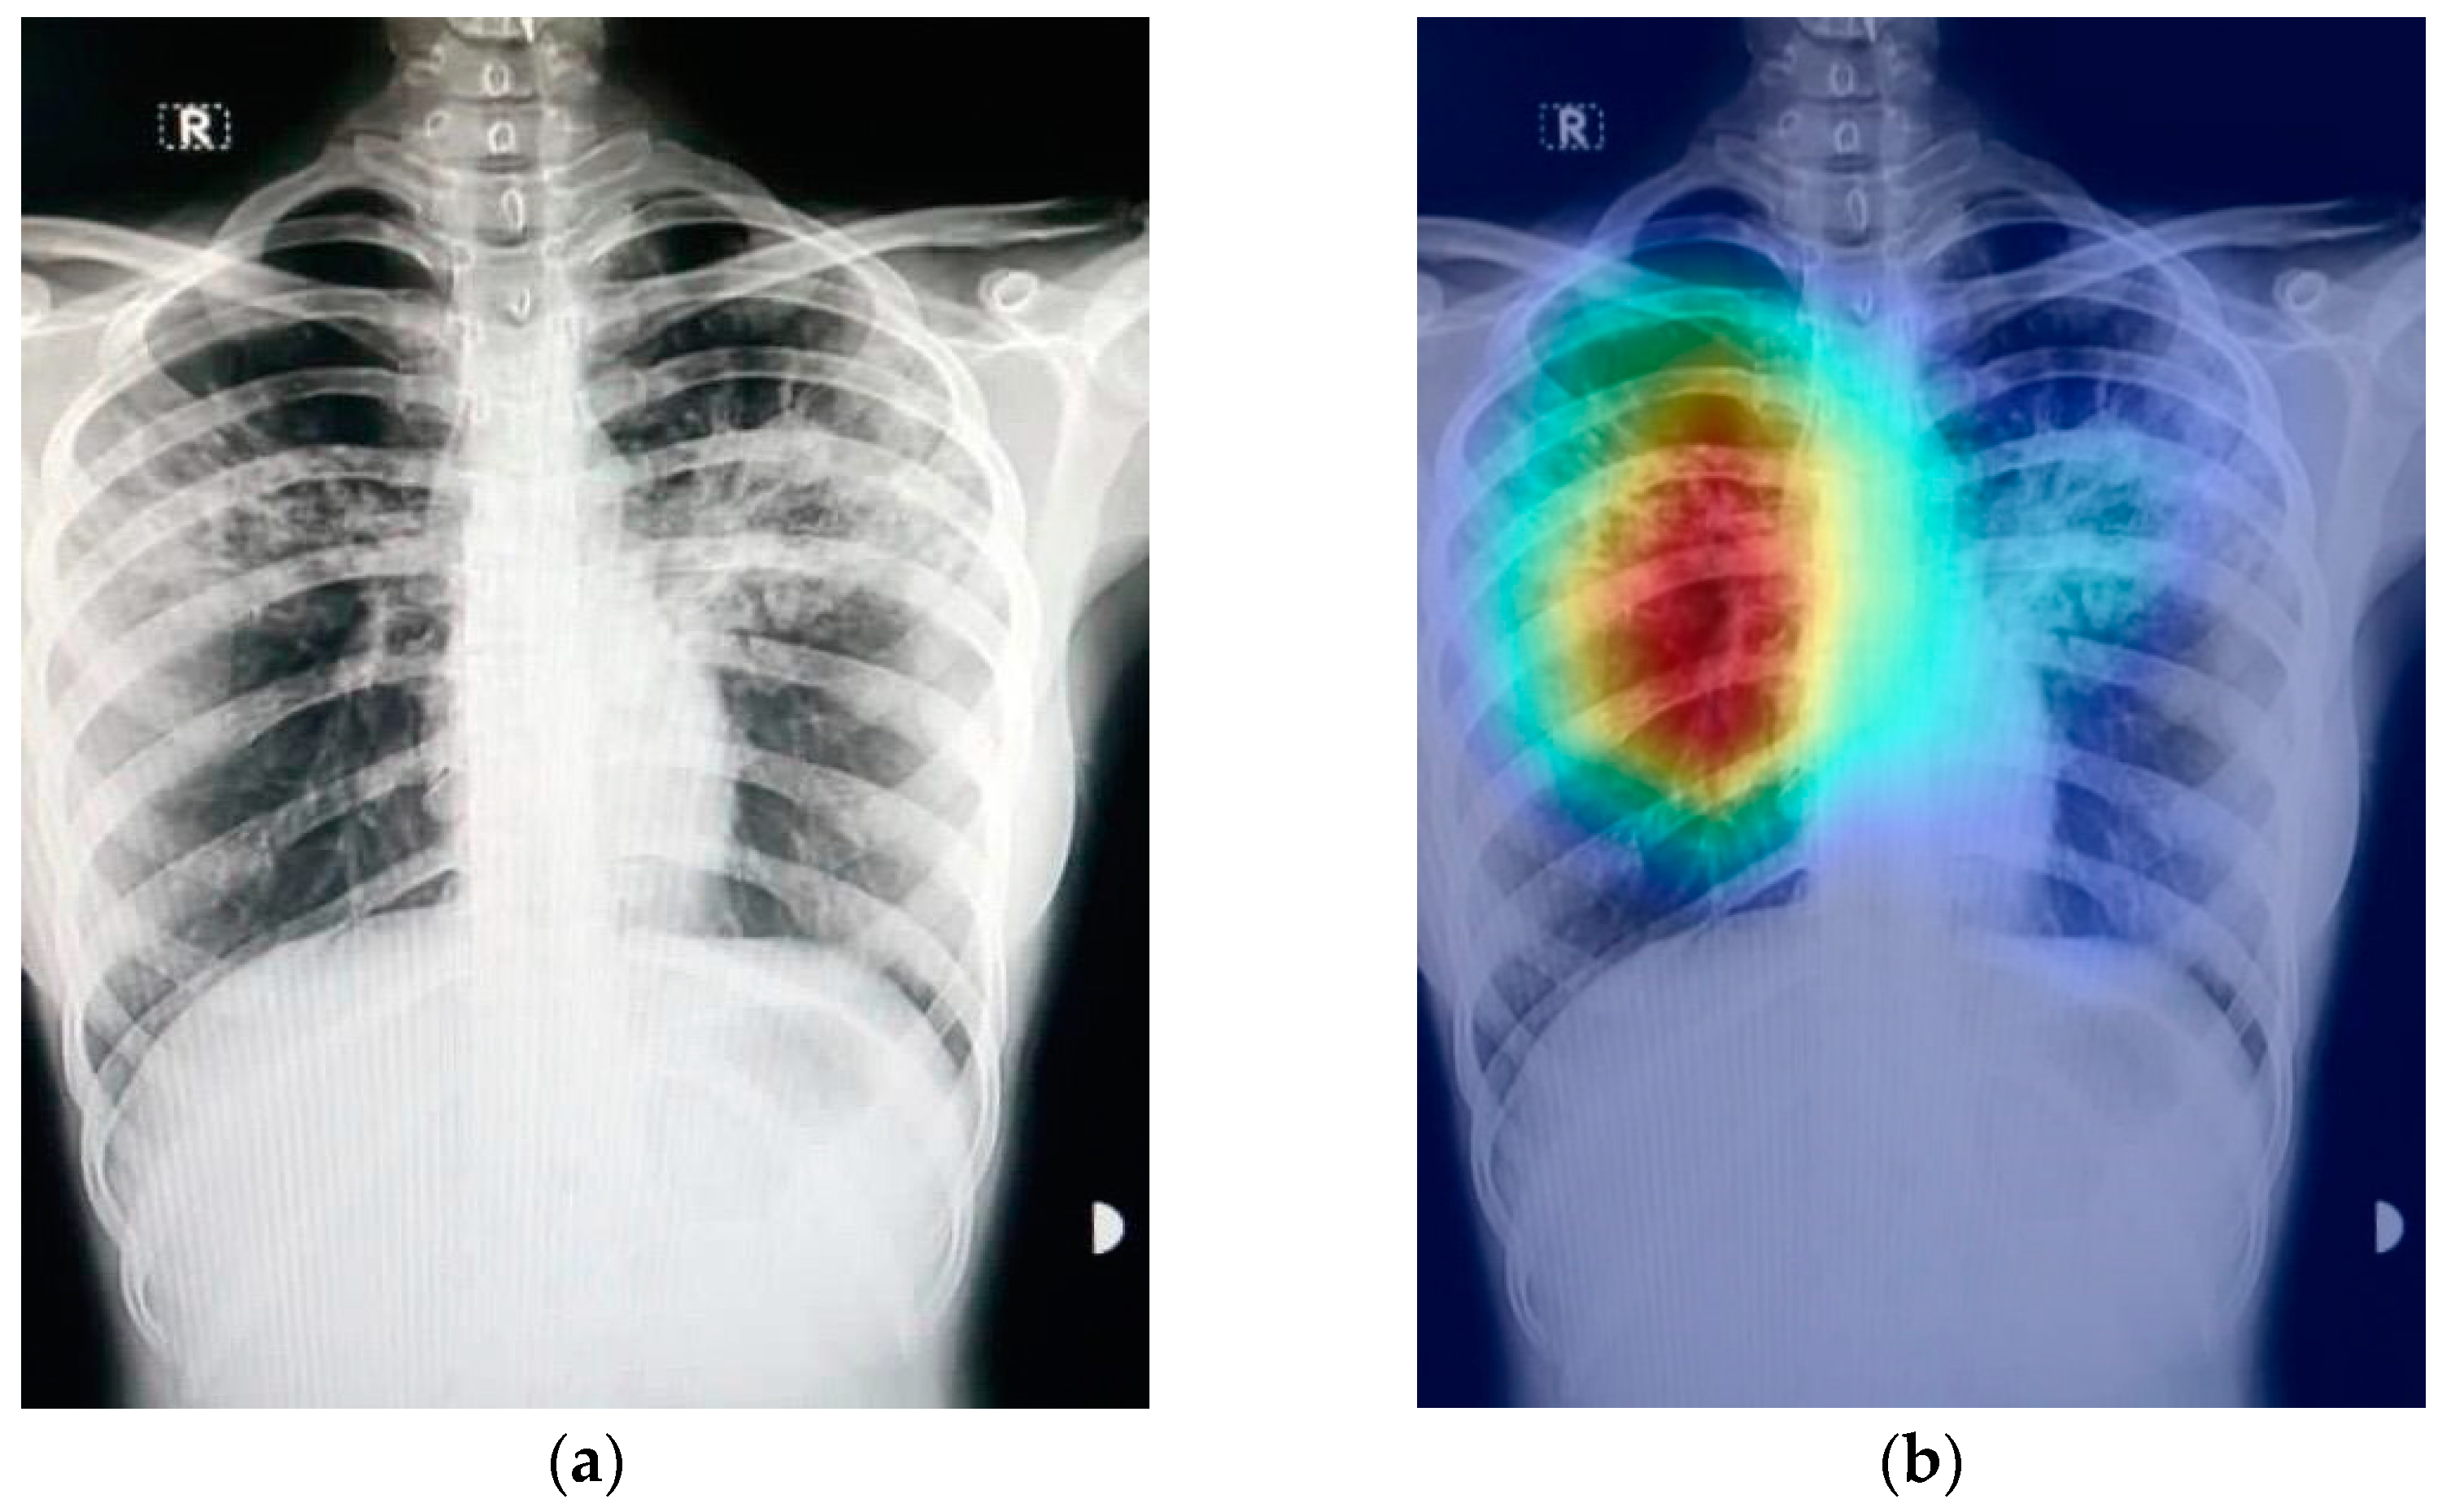

Figure 9 shows an example of a chest X-ray image generated using the Grad-CAM technique. The original chest X-ray image is shown in Figure 9a, whereas the overlay heatmap on the input image is shown in Figure 9b. The jet color scheme is used in this study. In this color scheme, blue tones represent lower values, which means that no features are extracted for a specific class, whereas the yellow and green tones represent medium values depicting quite less feature extraction, and the red and dark red tones represent larger values, i.e., the features in the region represent the specific class.

Figure 9.

Grad-CAM technique results on the COVID-19 X-ray image: (a) COVID-19 X-ray image; (b) Grad-CAM of the image.